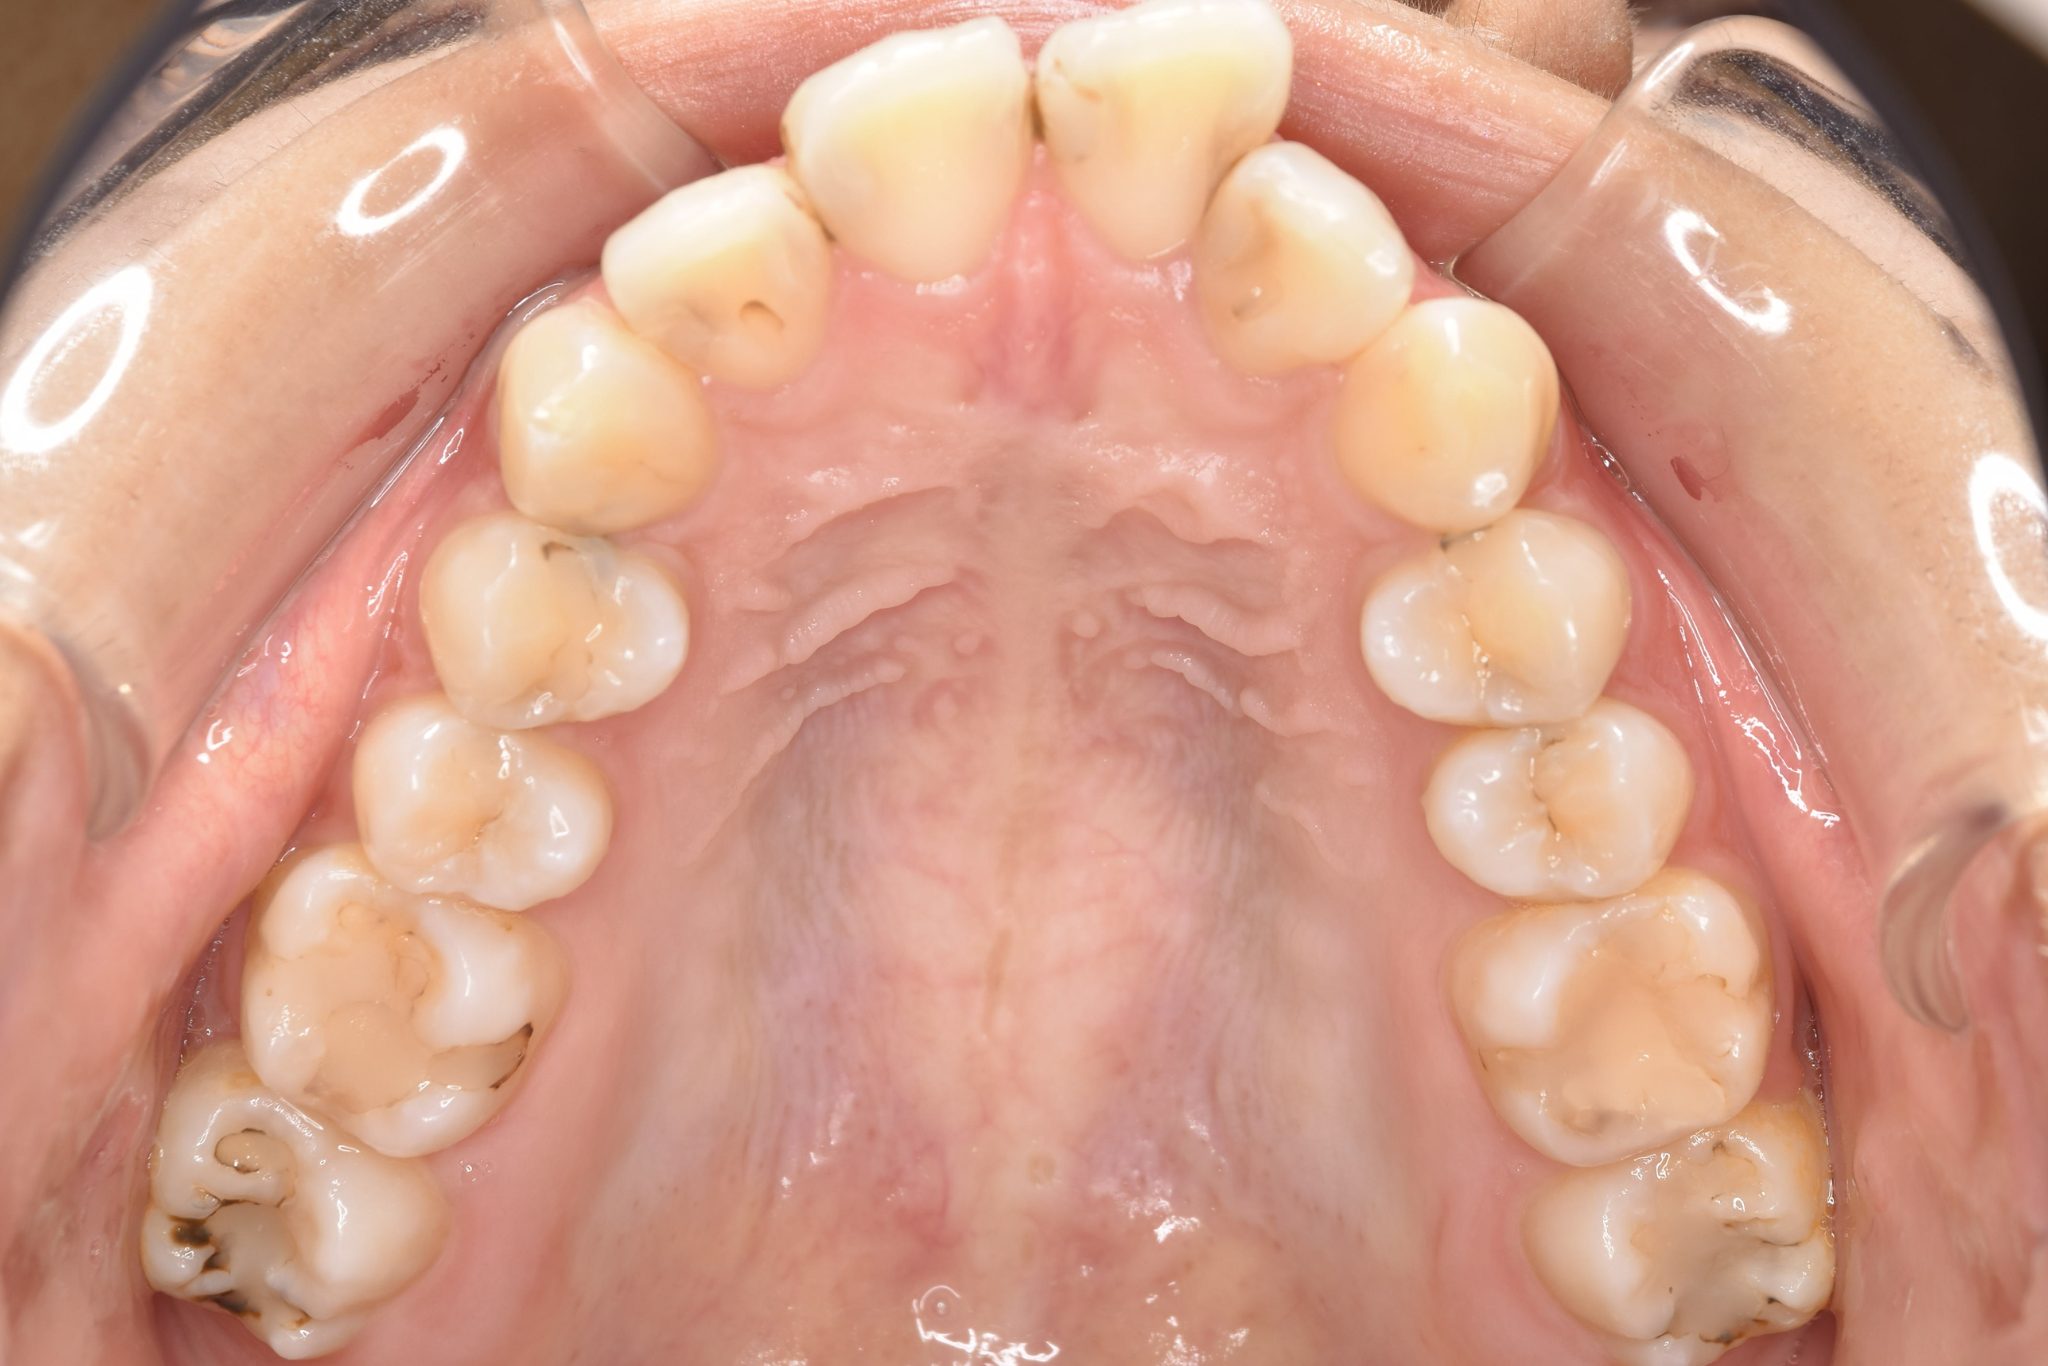

ビフォー

主訴 出っ歯

施術内容 MSEと下顎リンガルアーチを用いて上下顎骨を拡大した。

その後マルチブラケット装置とミニインプラントを用いて非抜歯で歯牙を配列した。

下顎前歯が1本先天性欠損であったが、良好な咬合を獲得した。口元の突出感と鼻閉症状は改善された。